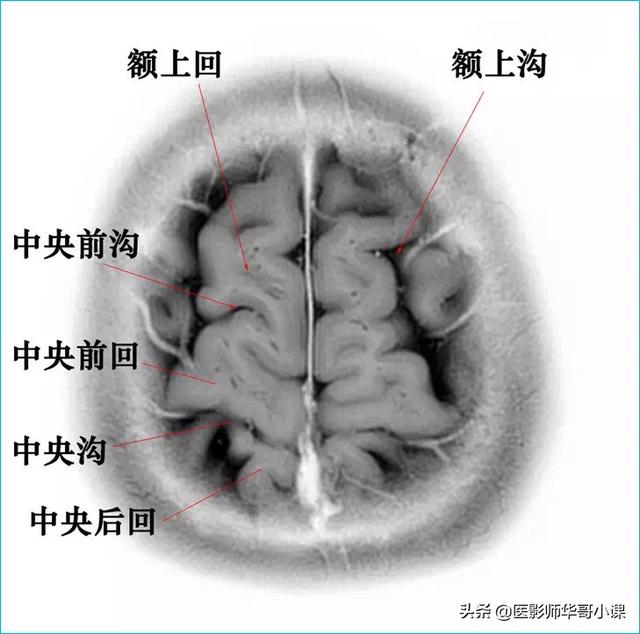

颅脑主要包括大脑、小脑、脑干、间脑,其中大脑又称为端脑,是人体的司令部,管辖人体的躯体活动、精神活动以及感觉行为等;脑干和小脑位于后颅窝的位置,脑干自上而下分为中脑、脑桥、延髓,脑干又称为生命中枢,对人体非常重要,因为脑干具有管辖呼吸和循环的初级生命中枢。其中大脑分为5个脑叶,分别是额叶、顶叶、颞叶、枕叶以及内侧面的岛叶。间脑分为上丘脑、下丘脑、后丘脑、背侧丘脑和底丘脑,背侧丘脑是一个重要的结构,是感觉传导路的重要中继站。颅脑包括颅骨和颅骨内的脑组织。颅骨由顶骨,颞骨,枕骨,额骨,以及颅底骨构成。颅骨构成的颅腔主要作用是保护脑组织。颅内的脑组织主要包括大脑,小脑,脑干。表面覆盖有软脑膜和硬脑膜,大脑分为左右两侧大脑半球,根据解剖位置又分为颞叶,枕叶,顶叶,额叶,各脑叶功能不尽相同。小脑也分左右半球。脑干分为延髓,脑桥和中脑三部分。